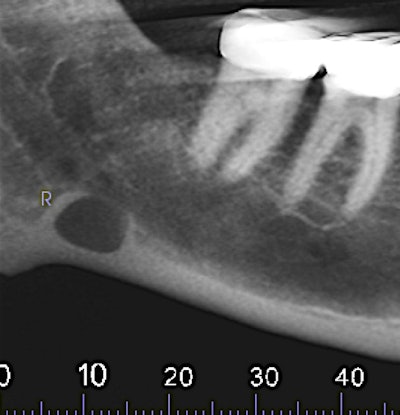

Figure 1: Reformatted and cropped panoramic film. All images courtesy of Dr. Juan F. Yepes.

Figure 2: Reformatted and cropped panoramic film.

The oral surgeon ordered a cone-beam CT (CBCT) exam. Click images below to enlarge. In order: reformatted panoramic radiograph and cropped image of the area of interest, coronal view of the posterior right mandible (the inferior alveolar canal in red), and 3D reconstructed image of the posterior right mandible.

A 63-year-old man presented to the oral surgeon after being referred by his family dentist because of an unusual radiolucency at the inferior border of the right mandible. Patient was asymptomatic. His past medical history included hypertension and high cholesterol, and he was taking lisinopril.

From the radiographic perspective, Stafne bone defects are radiolucent lesions, well-defined and well-corticated, oval in shape, and located below the inferior alveolar canal. No expansion is usually observed in the coronal views.